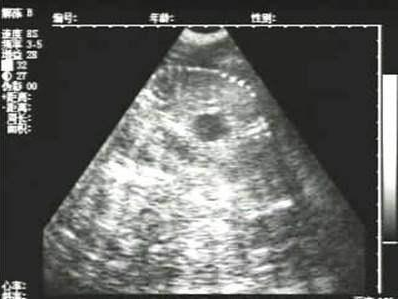

豬用B超機檢測有胎兒圖像

需要注意的是,出現(xiàn)云團狀必須雙側(cè)檢查加以確認.根據(jù)B超機顯示圖我們大致可以判斷孕齡.圖像呈橢圓或者卵圓形大致為30天左右孕齡;圖像呈橢圓形或者卵圓形外,有明顯發(fā)亮骨骼圖像大致為50孕齡左右;圖像囊胚消失,發(fā)亮處隱約可見竹節(jié)狀東西為成型胎兒骨骼,一般為后期80孕齡以后。一般B超機成像會出現(xiàn)三種顏色,白色、黑色、灰色。白色為密度較高的物體,如骨骼或者結(jié)實.黑色一般為液體,包括血液、羊水、組織間隙液體、炎癥病灶等。灰色一般為實質(zhì)性物質(zhì),如肌肉。